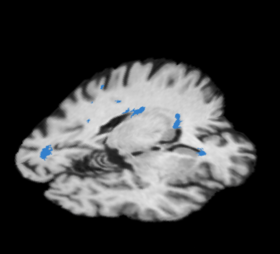

Slicer3 Module Lesion Classification

Lesion Classification Result

• The pipeline attempts to solve the problem of segmenting white matter lesions in Neuropsychiatric Systemic Lupus Erythematosus(NPSLE). The automated capability is aimed at clinical researchers using Slicer3 software. The utility of having accurate lesion labels permits summary of perfusion within lesions, correlation of lesion load by location with neuropsychiatric symptoms, and summary of structural image intensities or DTI scalars within lesion boundaries.